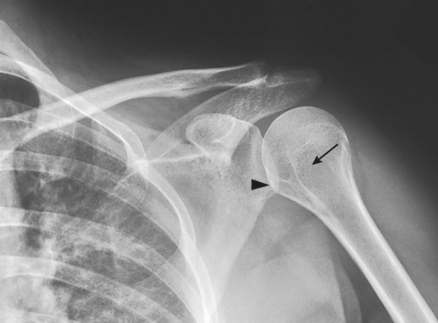

• Anterior dislocation of the humeral head can result in a wedge-shaped compression fracture of the articular surface of the humeral head, called the Hill-Sachs defect.1 The fracture is located on the posterolateral humeral head. An exaggerated external rotation of the arm may be required to see the defect.

• Assist the patient in rotating the arm to avoid overstressing the shoulder joint.

Structures shown: An inferosuperior axial image shows the proximal humerus, the scapulohumeral joint, the lateral portion of the coracoid process, and the AC articulation. The insertion site of the subscapular tendon on the lesser tubercle of the humerus and the point of insertion of the teres minor tendon on the greater tubercle of the humerus are also shown. A Hill-Sachs compression fracture on the posterolateral humeral head may be seen using the Rafert modification (Figs. 5-29 and 5-30).

Fig. 5-29 A, Inferosuperior axial shoulder joint: Lawrence method. B, Inferosuperior axial shoulder joint: Rafert modification showing Hill-Sachs defect (arrow). C, Coronal MRI of shoulder joint showing Hill-Sachs defect (arrow) after recurring shoulder dislocation. (A and B, From Rafert JA et al: Axillary shoulder with exaggerated rotation: the Hill-Sachs defect, Radiol Technol 62:18, 1990. C, From Jackson SA, Thomas RM: Cross-sectional imaging made easy, New York, 2004, Churchill Livingstone.)